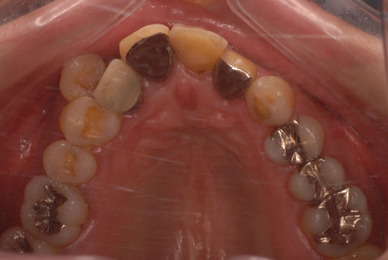

歯をいじられ体も心もボロボロになった患者さんからの手紙です。マスコミや権威などがいかにいい加減かわかります。歯は触らないほうがよろしいのです。

昭和60年代ぐらいから、私は歯を触るとか矯正するとかマウスピースをして顎の関節の症状を治癒するなどというような処置はしなくなってきました。

そもそも歯を触り何らかの金属やセラミックを入れる行為そのものが医学的には傷害処置ですから、なるべく避けるべき物なのです。